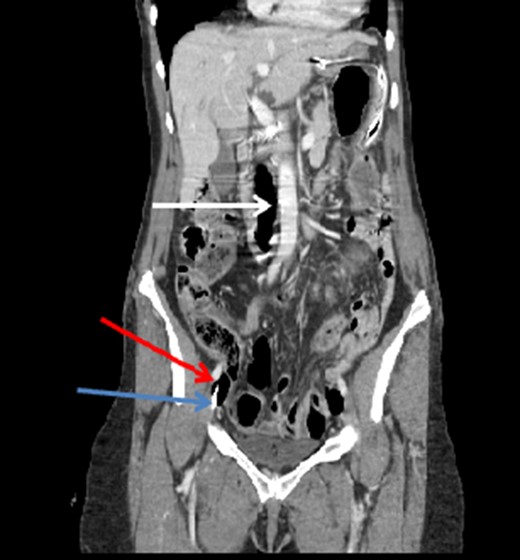

Coronal CT image of the abdomen and pelvis showing a significant amount of air within the IVC (white arrow). Note the CVC (blue arrow) and additional air (red arrow) in the right external iliac vein.